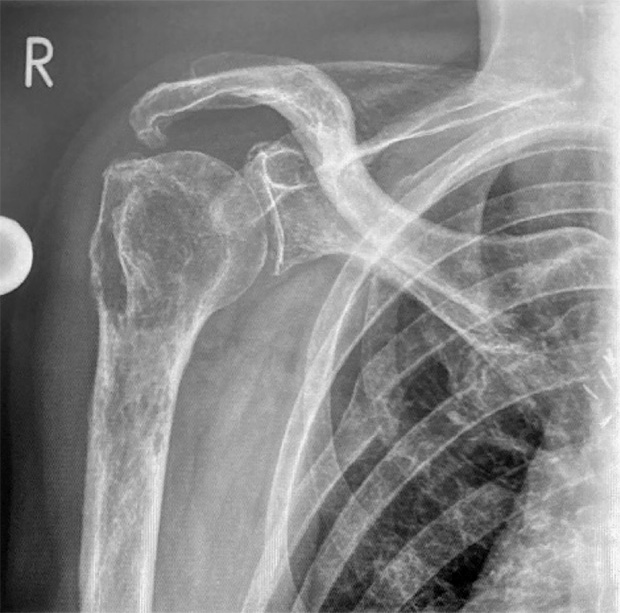

Pre-op

Pictures 1 and 2: X-ray a-p and MRI

Patient:

- 73 year old male with bone tumor in the proximal humerus right side